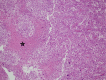

Subependymal giant cell astrocytoma is a benign WHO grade I intraventricular tumor arise in patients with tuberous sclerosis complex. Previous reported described histopathological predictors of more aggressive forms, terms atypical SEGA in infantile age group. Other reports showed possible transformation of SEGA into glioblastoma, or misdiagnosis as glioblastoma due to the presence of atypical histopathological features. Here, we report a case of an infant who presented with right frontal extraventricular SEGA and underwent craniotomy with complete resection. Eight months later, he presented with fast recurrence in same location with midline shift and subfalcine herniation. Histopathological description showed high grade features including Ki labeling index of 60%, atypical mitotic figures, cellular plemorphism and necrosis. We also discussed the possible presence of different entity (termed atypical SEGA) which may have more aggressive clinical course, with literature review of predictors of SEGA aggressiveness and possible transformation/misdiagnosis as glioblastoma.